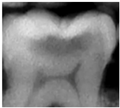

| 0 | Sound![]() | No shadow![]() | No radiolucency![]() |

| 1 Early | First Visual change in enamel![]() | Thin grey shadow into enamel![]() | Radiolucency in outer half of enamel![]() |

| 2 Distinct | Distinct Visual change in enamel ![]() | Wide grey shadow into enamel![]() | Radiolucency in inner half if enamel +/- Enamel dentin junction![]() |

| 3 Distinct | Localized enamel breakdown![]() | Shadow less than 2mm in dentine![]() | Radiolucency limited to outer 1/3 of dentine![]() |

| 4 Distinct | Underlying dentinal shadow![]() | Shadow more than 2 mm in dentine![]() | Radiolucency passed 1/3 of dentine![]() |